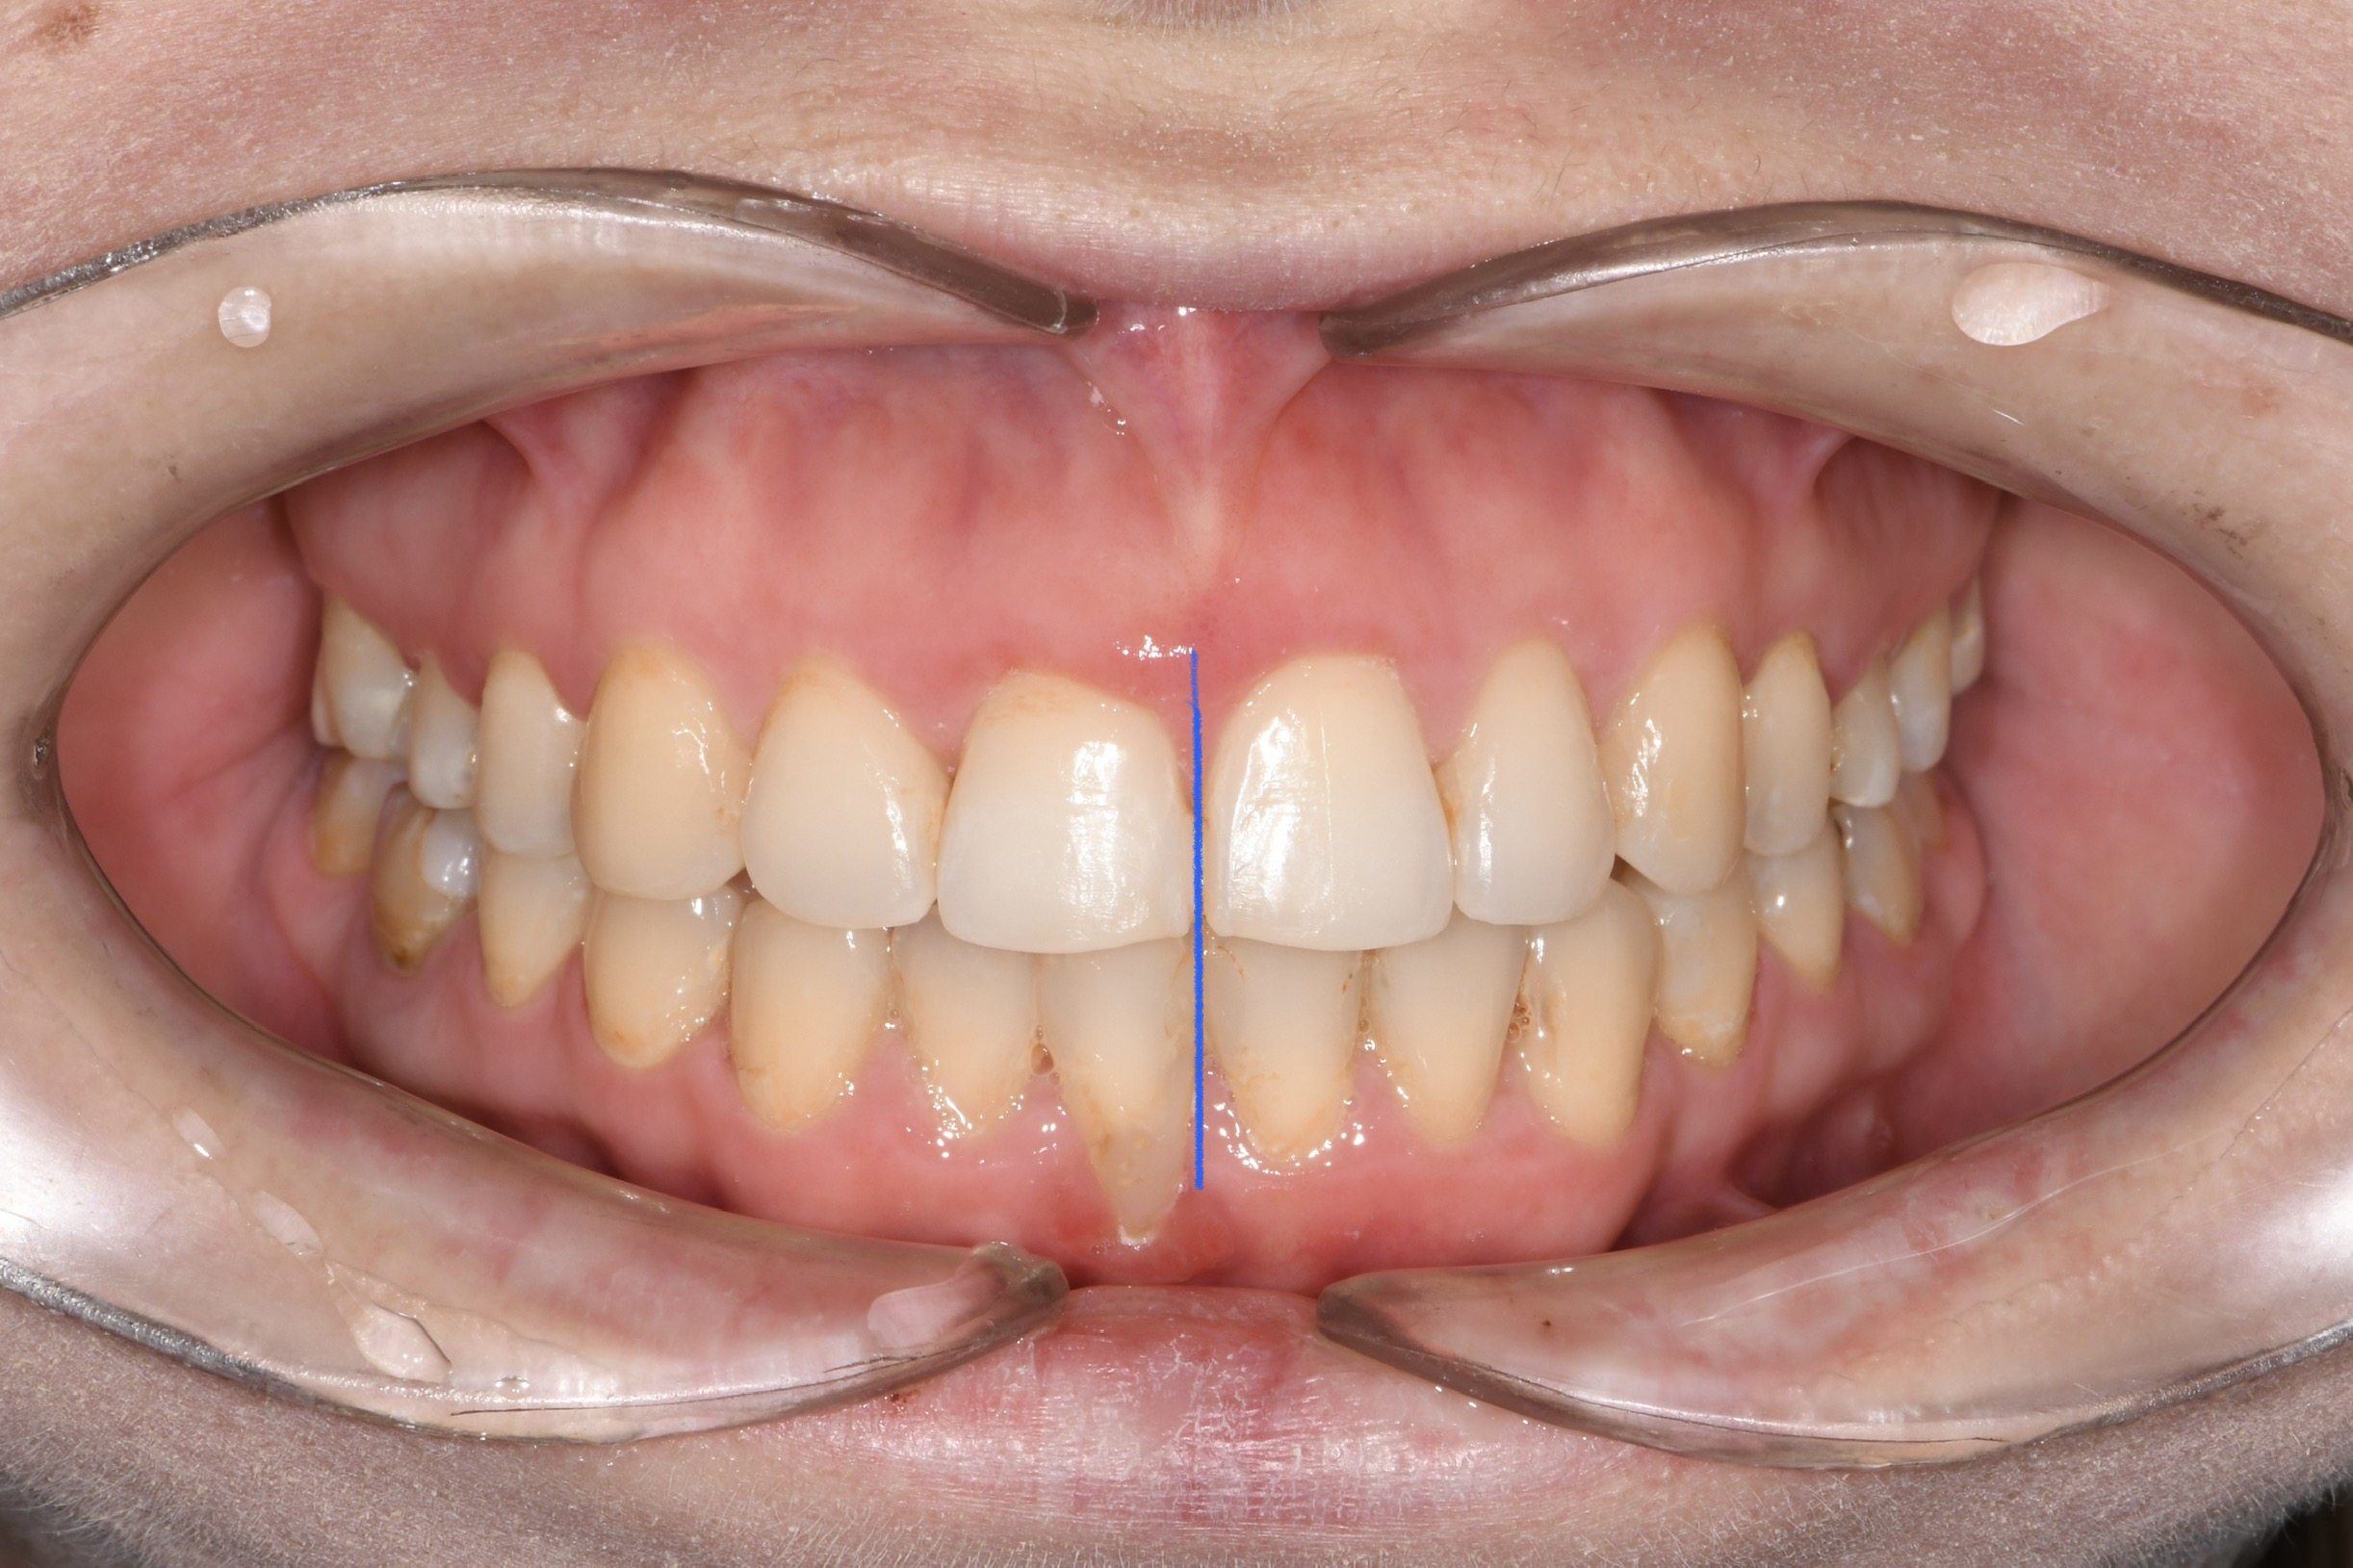

Az elmúlt évekből rengeteg szakmai referenciát tudnánk bemutatni, amelyek különböző fogszabályozási problémákat oldottak meg. Válogatva a több száz esetből, ezen az oldalon olyan képeket, információkat igyekeztünk bemutatni, amelyeknek a segítségével a jövőbeni pácienseinknek azt tudjuk üzenni: A Te fogsorod is lehet gyönyörű!

(Képeket a Pácienseink külön írásos beleegyezésével mutatjuk be!)